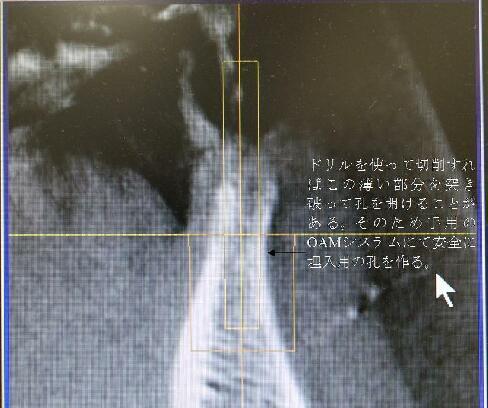

下顎の前歯の2番目の側切歯の位置へのインプラント埋入手術のCT写真上でシュミレーションして いるところです。3ミリのインプラント体を埋入するには骨が薄すぎます。ドリルでの切削では外側の壁に穴が開いたりドリルが突き抜けたりします。大変危険ですが多くの大学病院や歯科医院ではドリリングで対応してるのが現状です。 当医院では専用の器具を用いて対応しています。 前面から見た写真です(オレンジ色の部位です)

横から見た写真です。